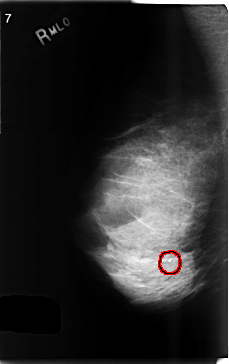

C_0501_1.RIGHT_MLO

FILE: C_0501_1.RIGHT_MLO.OVERLAY

TOTAL_ABNORMALITIES 1

ABNORMALITY 1

LESION_TYPE CALCIFICATION TYPE DYSTROPHIC DISTRIBUTION CLUSTERED

ASSESSMENT 3

SUBTLETY 5

PATHOLOGY BENIGN

TOTAL_OUTLINES 1

BOUNDARY